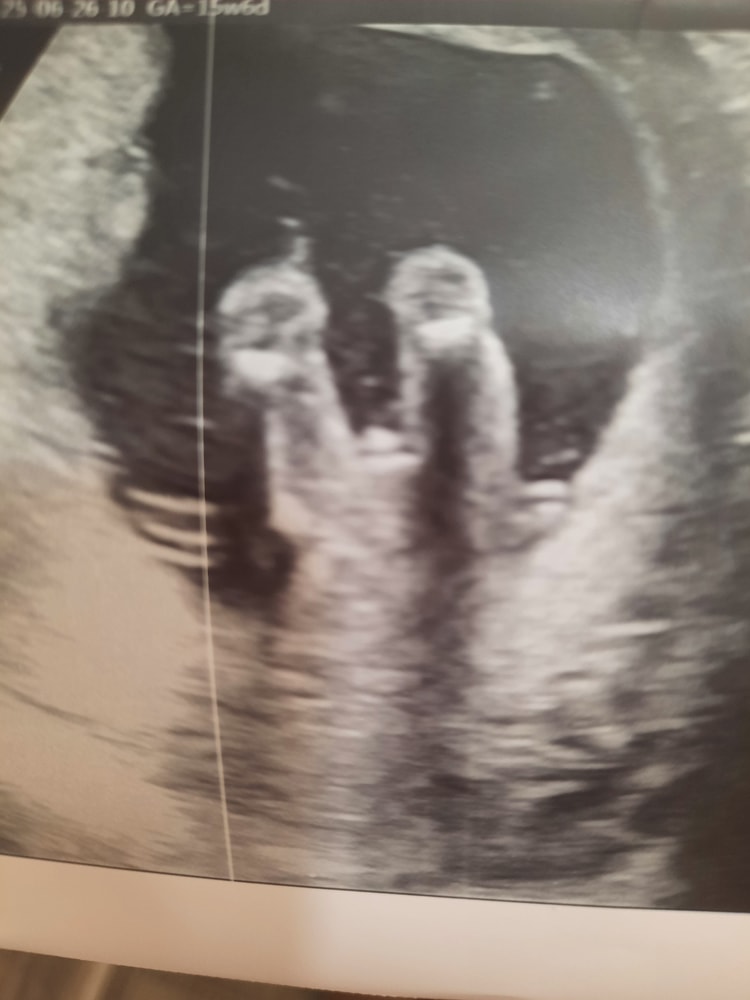

УЗИ на 15.5 неделе. Точно мальчик?

Врач сказал, что мальчик. А что думаете вы?

Вроде, на таком сроке уже кофейное зёрнышко торчать не может

Тож думаю что мальчик,у меня так ж было на 15нед